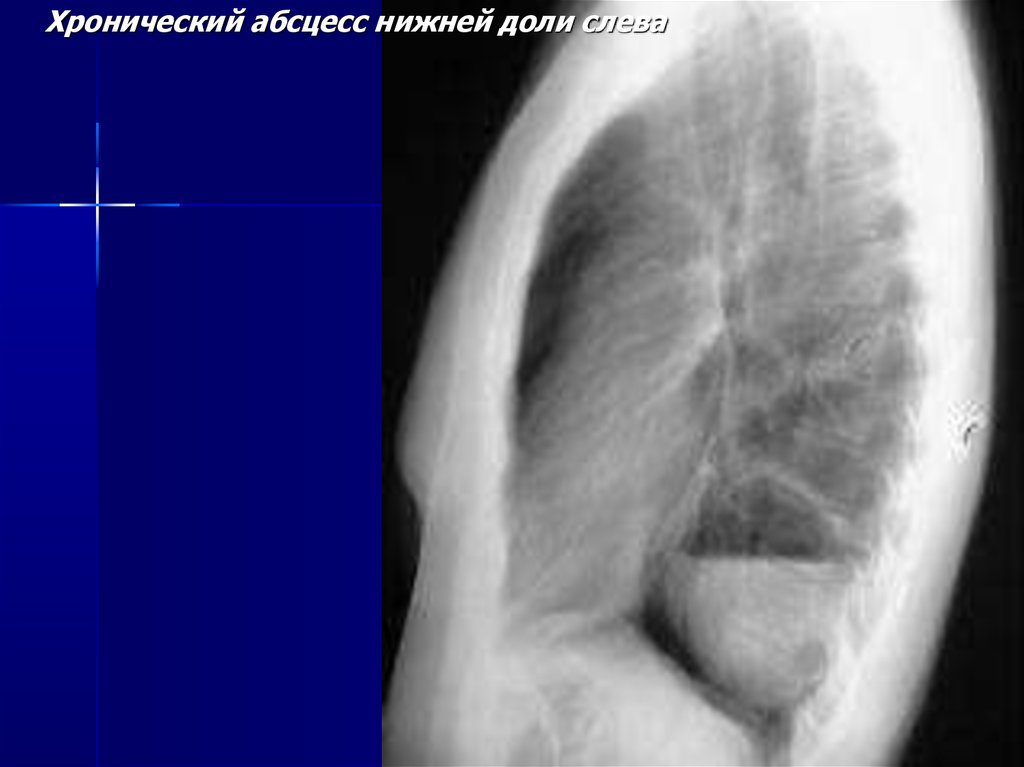

Хронический абсцесс нижней доли слева